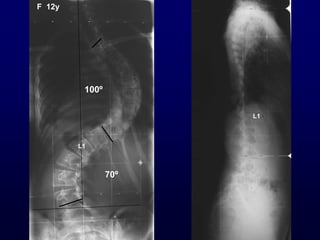

Χεηνμονγηθή ζεναπεία

Γκδείλεηξ

• Ηονηώμαηα > 45°

Γλαίνεζε : Balanced δηπιά θονηώμαηα < 55°

Πνμεγπεηνεηηθόξ έιεγπμξ

• MRI Οζθοαιγία, αοπεκαιγία

Κεονμιμγηθό έιιεημμα

Ηαηώηενμ (ΑΡ) θύνηςμα

< 10 εηώκ

L1

70º

100º

F 12y